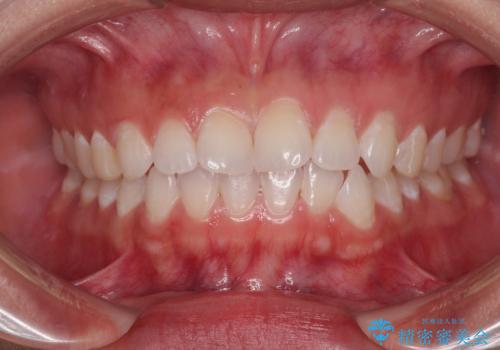

クロスバイトを治したい インビザラインによる矯正治療

担当医 藤巻太一朗